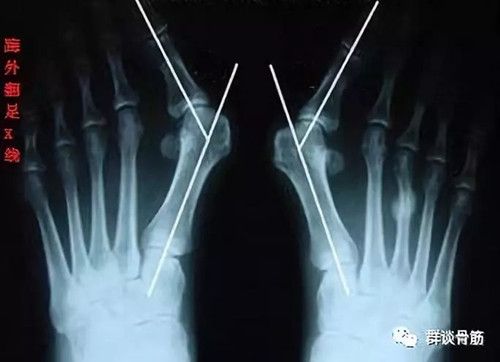

“踇外翻”长什么样?

踇外翻,俗称“大脚骨”,是指踇趾在第一跖趾关节处向外侧偏斜移位。踇外翻是累及踇趾的最常见的病变,多见于中老年妇女,最常发生在有遗传倾向加上长时间穿不合适的鞋子的人,不合适的鞋子会对踇趾施加异常压力。

踇僵硬一般表现为踇趾在第一跖趾关节处向外侧偏斜,关节内侧出现明显的骨赘,一些患者骨赘处软组织因长期受鞋子摩擦挤压而出现红肿、积液,称为踇囊炎。